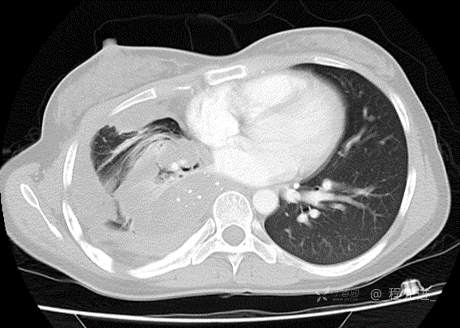

患者性别:女

患者年龄:26岁

简要病史:反复胸闷、气喘、咳嗽半年